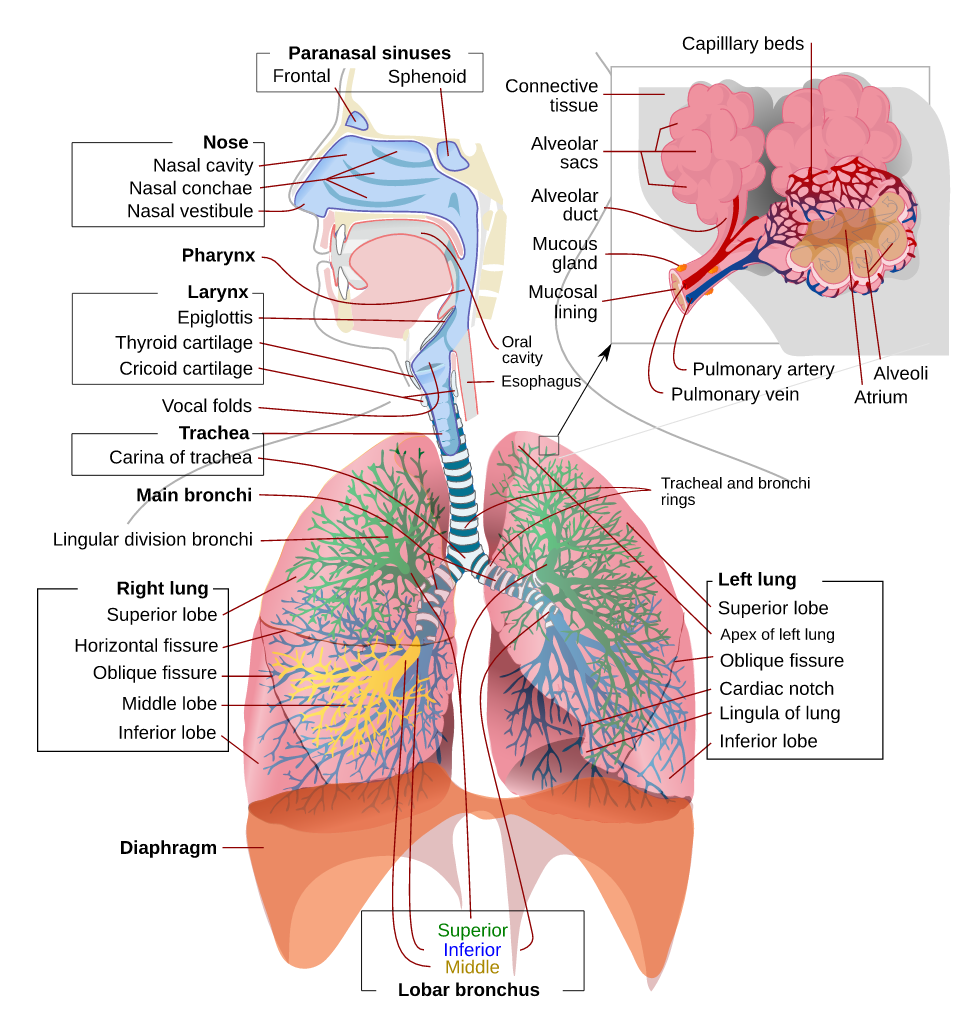

1 – Review of Respiratory System Anatomy